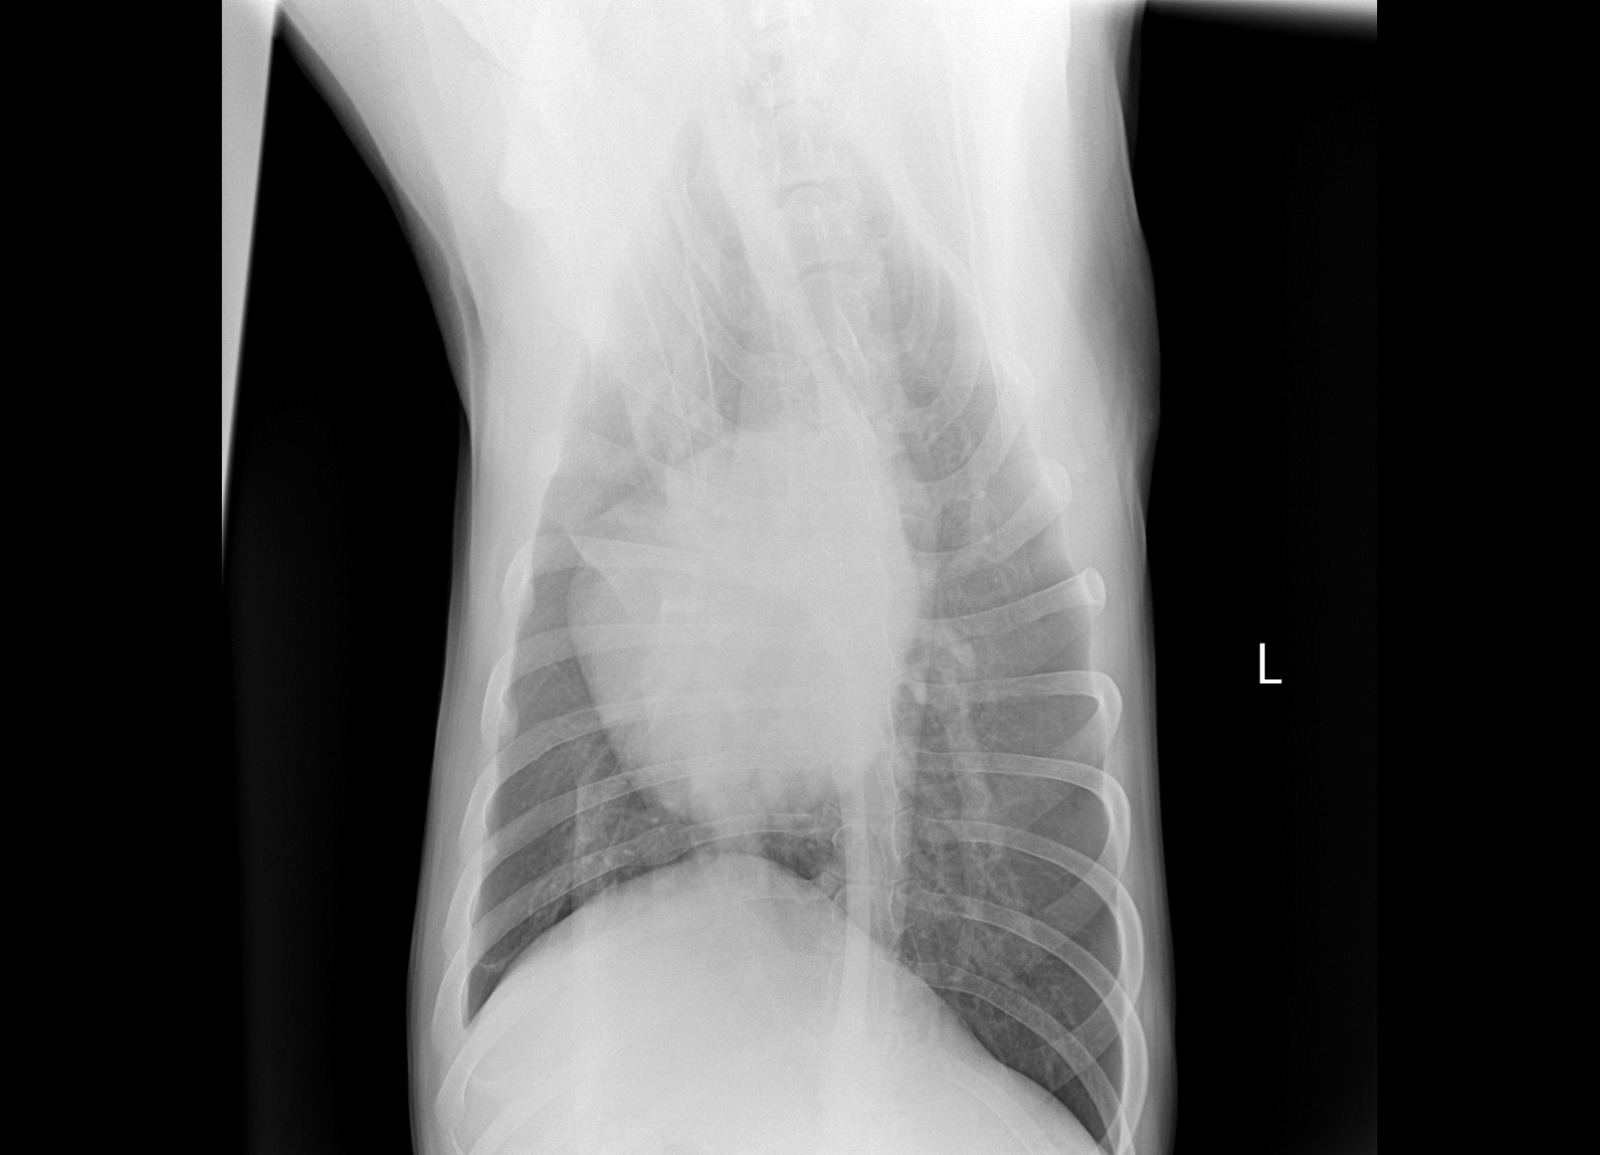

Рентген

Описание рентгена

Интересно, а изменения в бронхах на рентгене от диро или результат хронического бронхита?